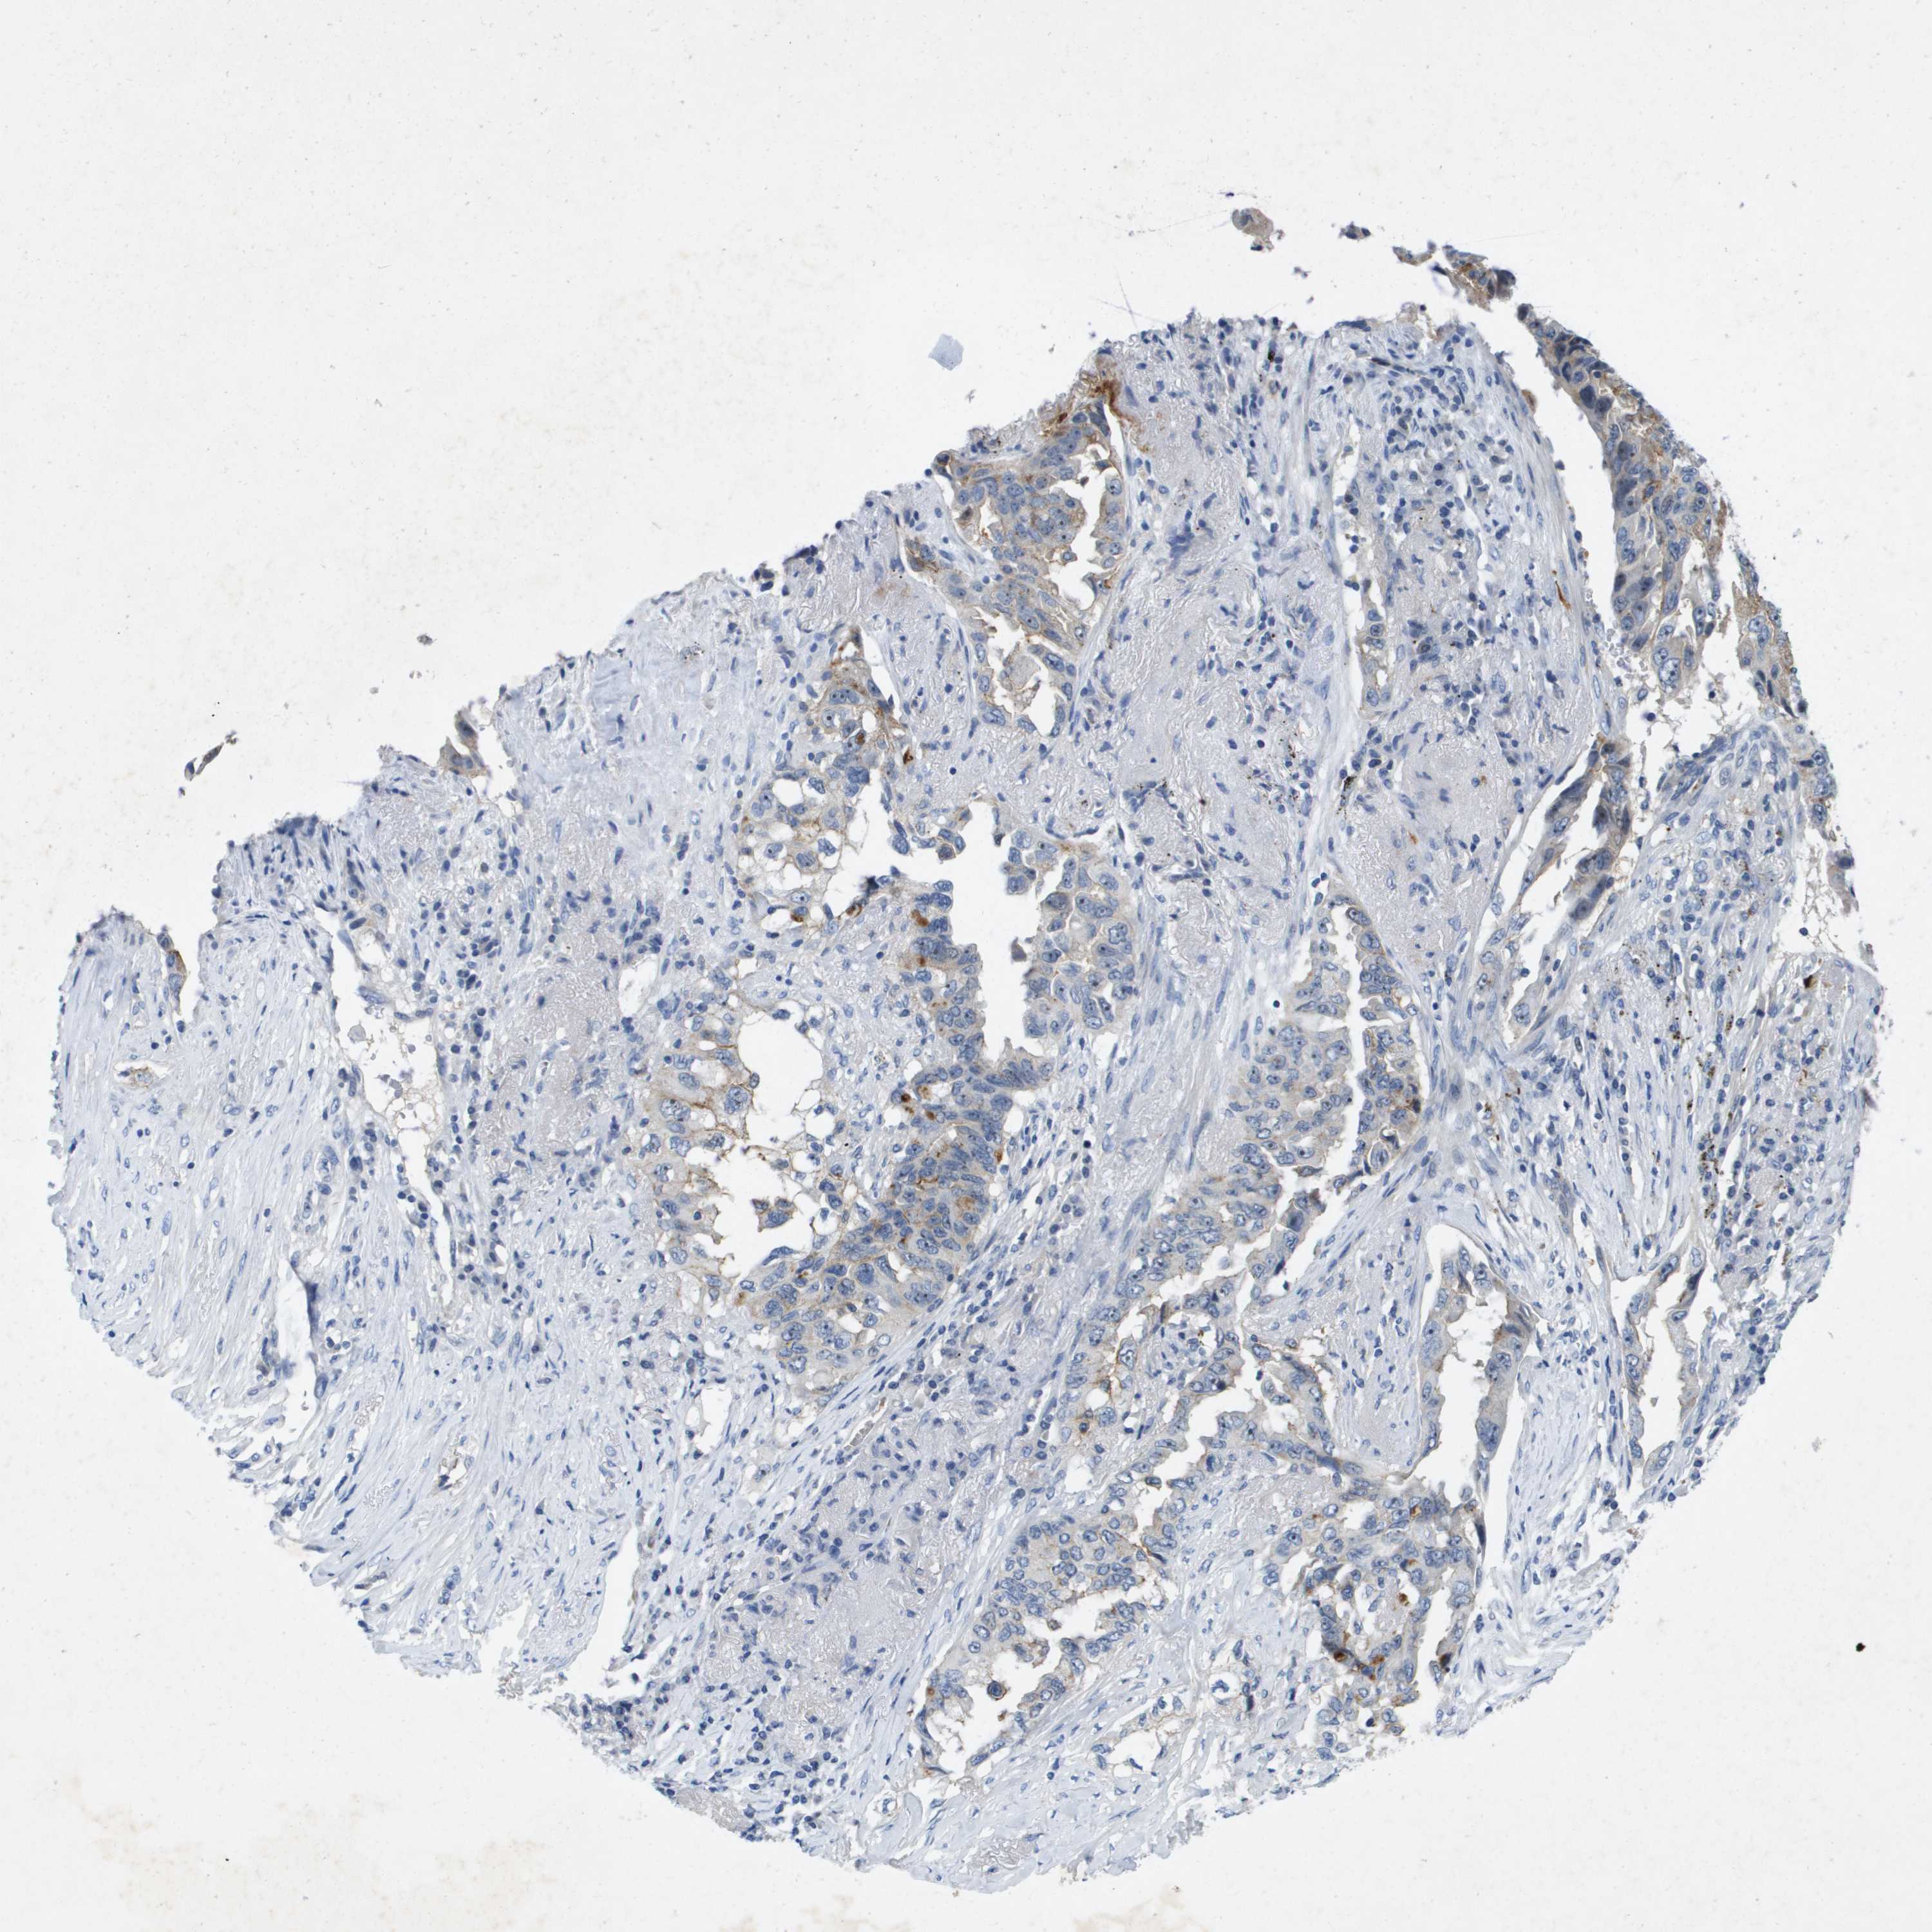

CANCER LUNG CANCER Show tissue menu

LUAD TCGA LUAD VALIDATION LUSC TCGA LUSC VALIDATION PROTEIN LUAD CPTAC PROTEIN LUSC CPTAC PROTEIN EXPRESSION

ANTIBODIES

AND

VALIDATION